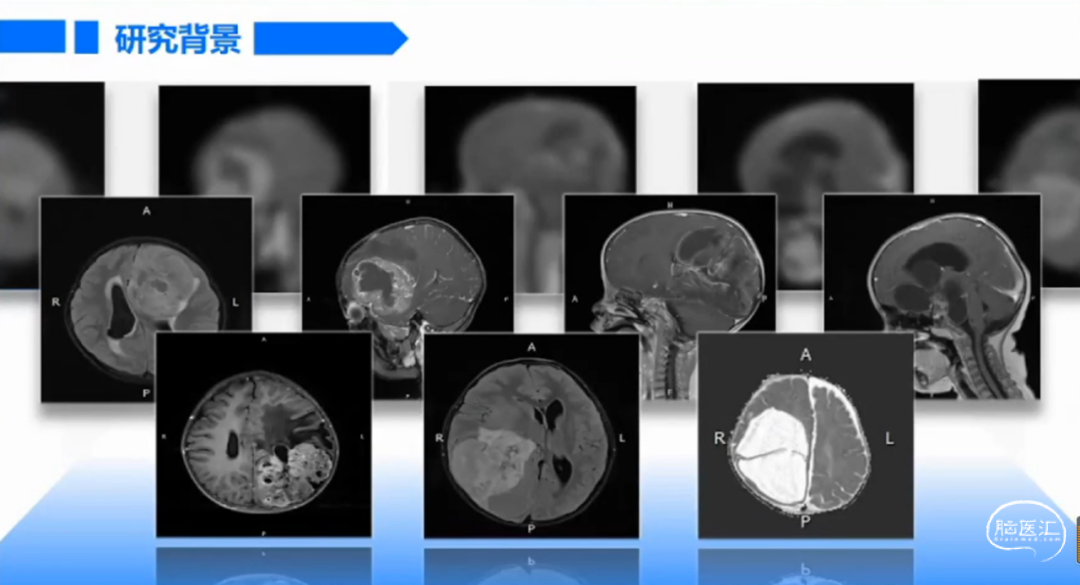

由上海交通大学医学院附属新华医院马杰教授在第十五届华东六省一市神经外科学术会议暨2021上海市医师学会神经外科分学会学术年会上带来的精彩内容:整块切除儿童脑肿瘤的方法探讨,欢迎阅读、分享!